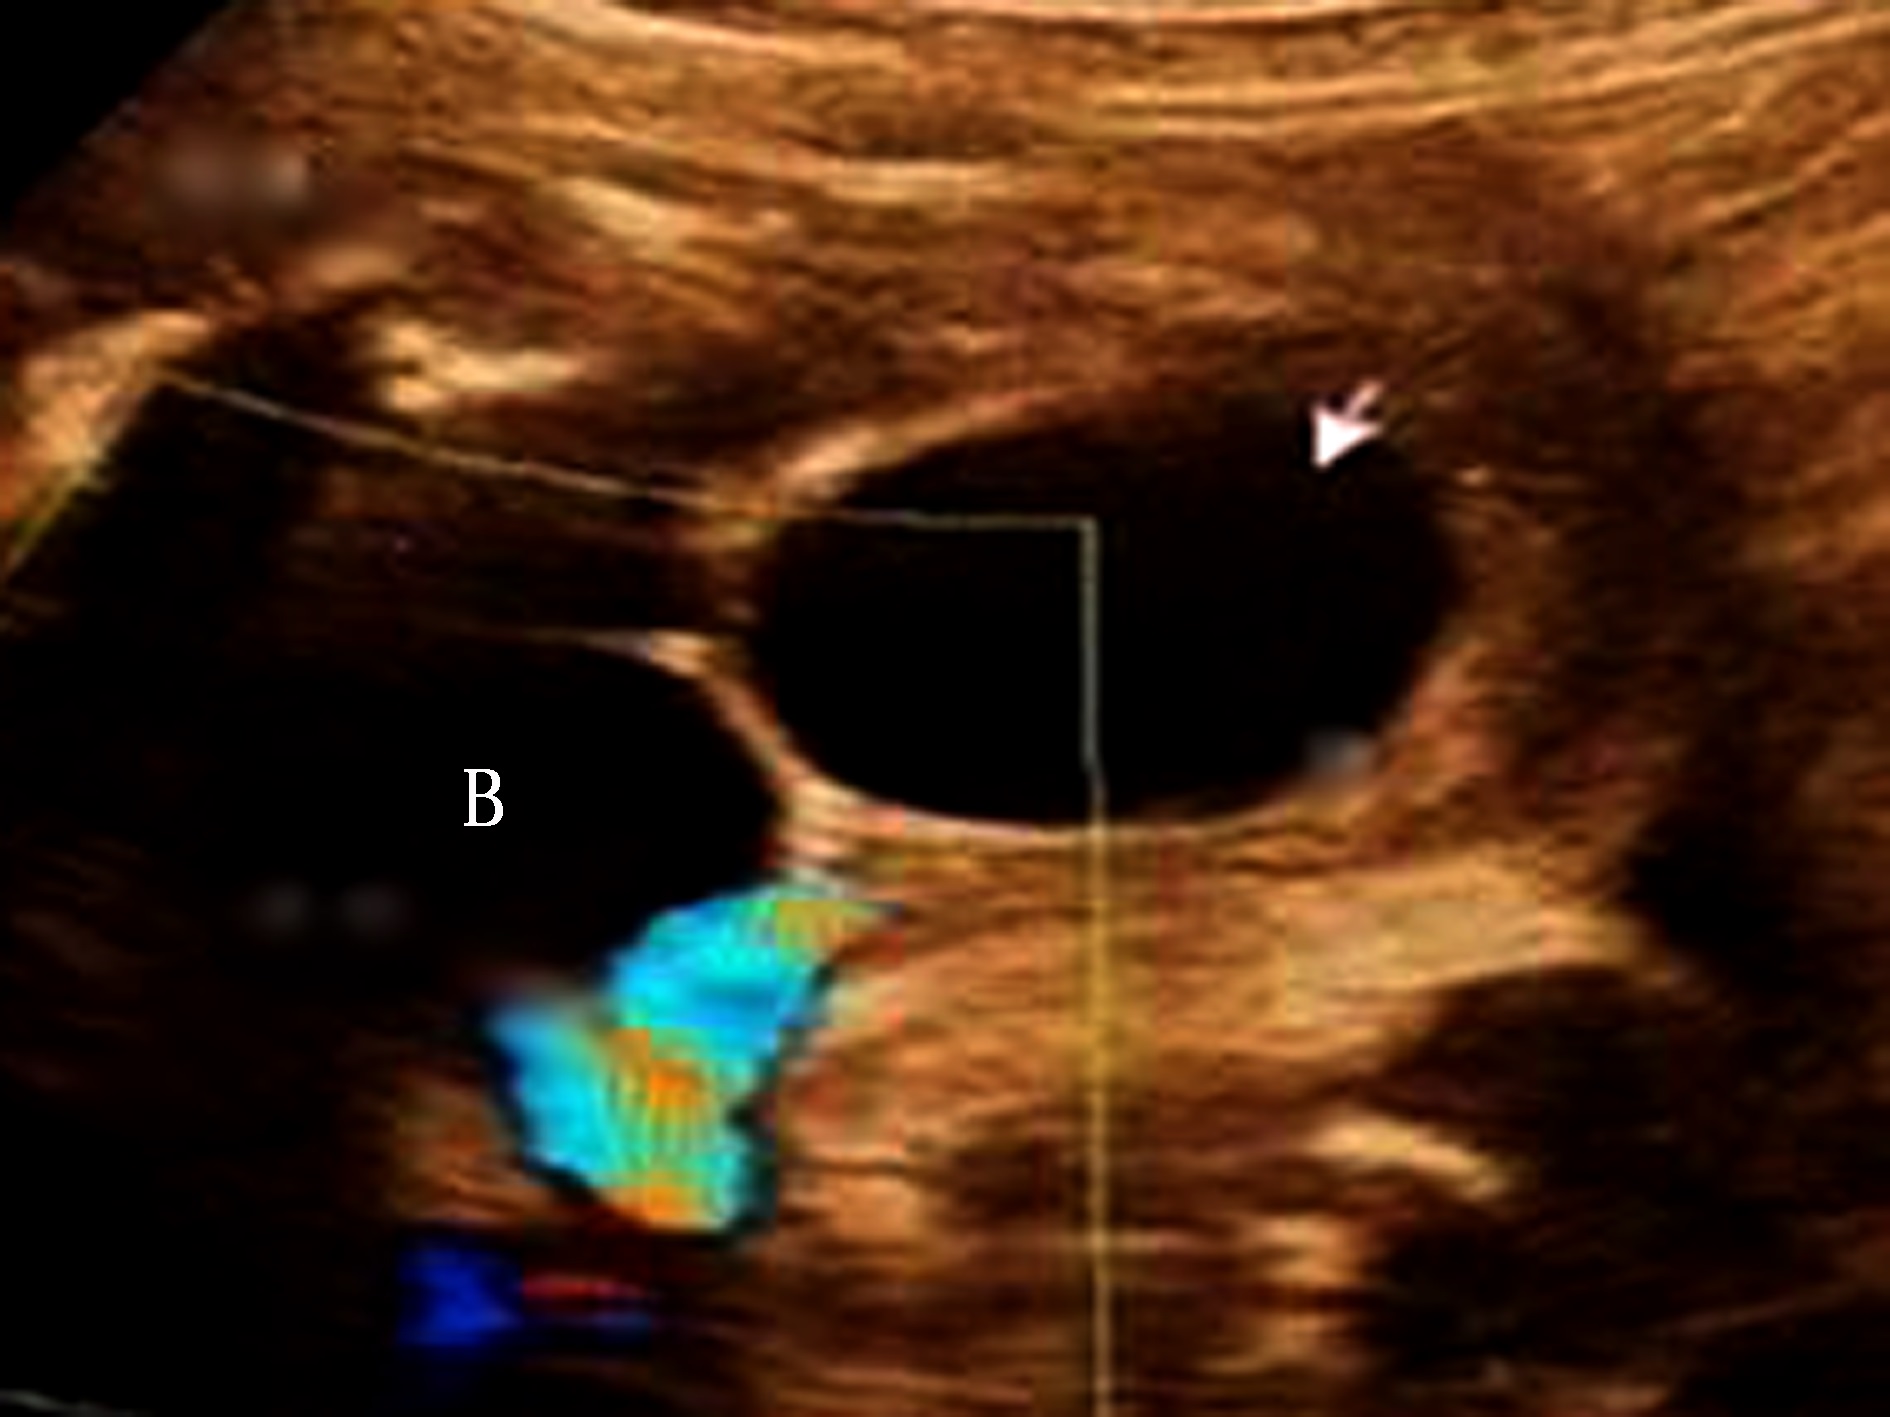

胎儿附件区囊肿是女性胎儿发现最多的腹部肿块之一,其发病率估计在1/2 600,多数为卵巢囊肿,其他还可见于胚胎遗迹囊肿。卵巢囊肿的成因是由于胎儿FSH、母体雌激素及胎盘hCG刺激的结果,有报道95%的卵巢囊肿为单侧。典型的卵巢囊肿超声表现为胎儿盆腔的囊状无回声,形态规则,边缘清楚,与膀胱相邻但不相通(图3),如果明确女性胎儿,则可以明确诊断。有报告最大直径可达10cm。

图3 孕30周胎儿卵巢囊肿(箭头)声像图